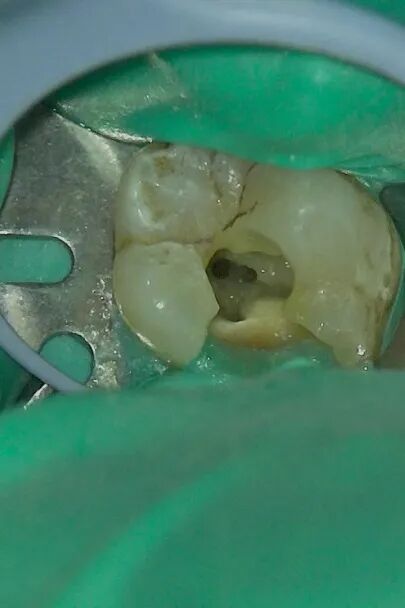

果不其然,在显微镜下,还发现了一条被“漏掉”细细的远中舌侧根管,打通了之后,一泡脓流出来了。“为了安全起见,另外三条根管的根充物也要取出来,清理干净,脓流出来之后我就确定问题出在哪了。”医生介绍。找到病根之后,在显微镜辅助下,医生为张女士进行2次根管治疗,将髓腔内的感染组织彻底清除干净,并做根管填充,这颗命途多舛的“病牙”重获新生,也没再发炎,张女士感激不已!

无“微”不至,直达病“根”,是显微根管治疗技术的优势,在放大2-30倍的显微镜下,光源充足、视野清晰,所有根管一览无余,医生能够清晰地看到根管内部的细微结构、形态、病变等情况,治疗过程中体验感更好。

“显微根管是显微镜技术和医学技术的完美结合,能够帮助医生观察到肉眼无法分辨的根管口和微小病损,提高整个操作过程的控制性。”在后期做根管充填时,也比肉眼下充填得更加严密